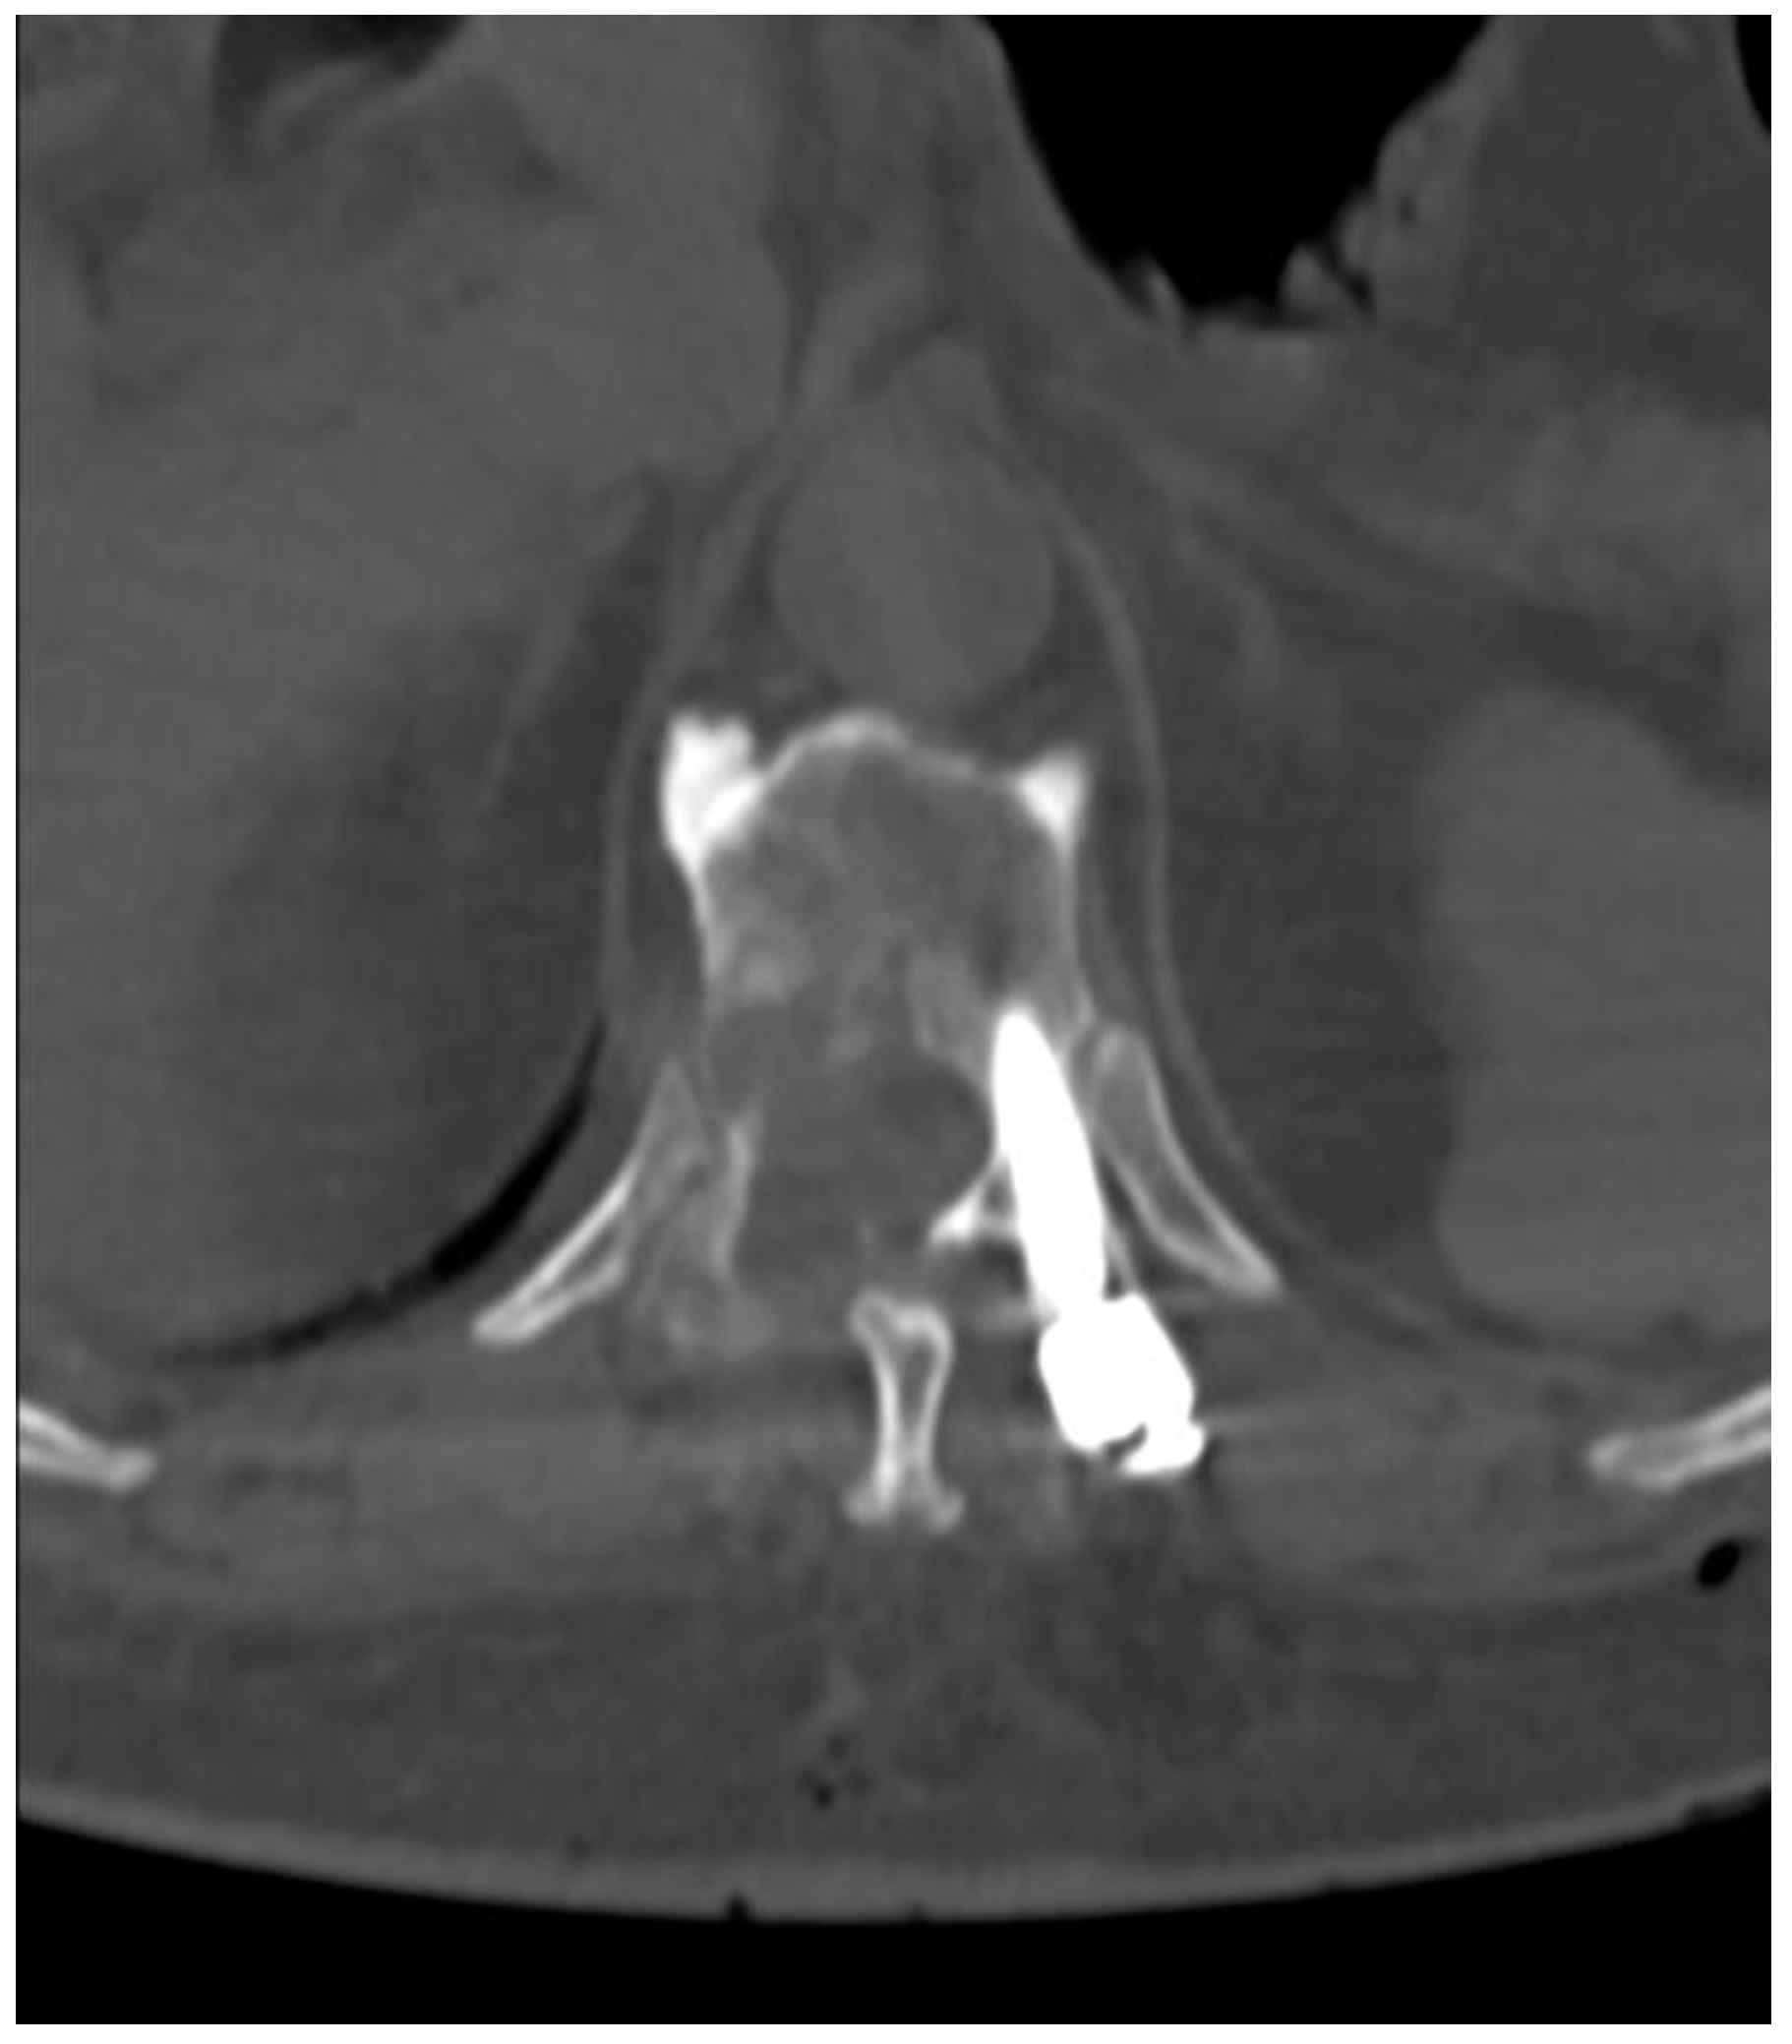

2. Materials and Methods

3. Results